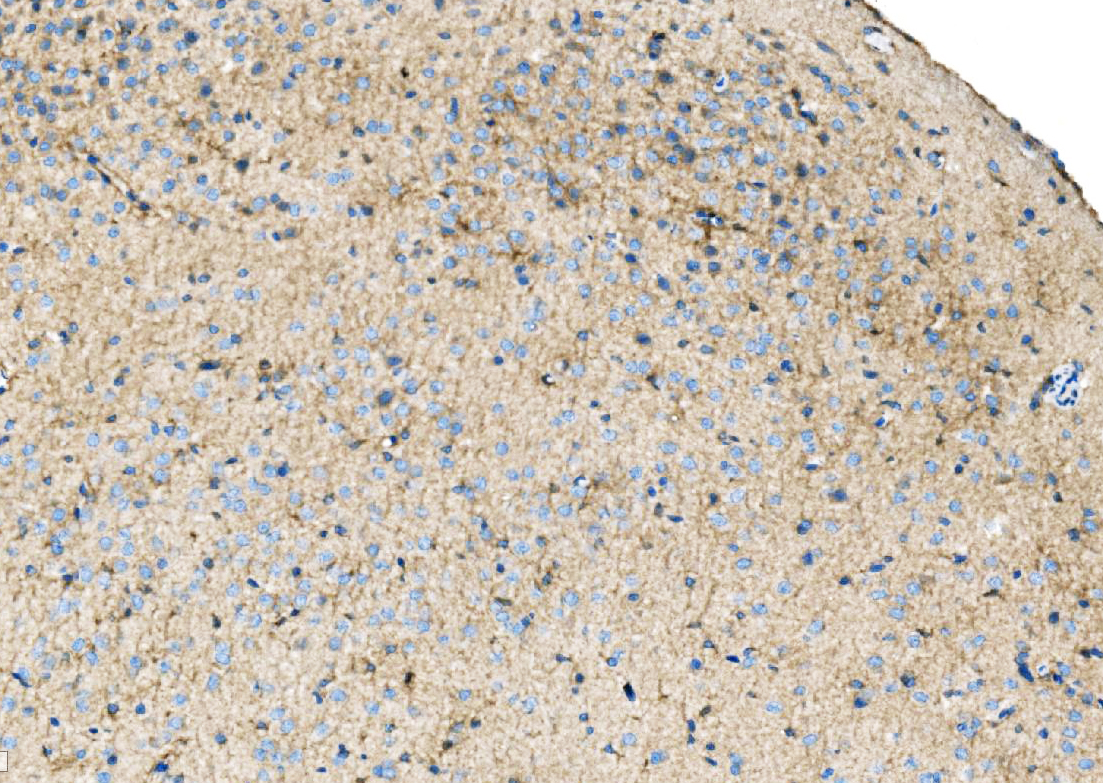

IHC analysis of Ezrin/EZR using anti-Ezrin/EZR antibody (A01750-2).

Ezrin/EZR was detected in a paraffin-embedded section of rat brain tissue. Biotinylated goat anti-rabbit IgG was used as secondary antibody. The tissue section was incubated with rabbit anti-Ezrin/EZR Antibody (A01750-2) at a dilution of 1:200 and developed using Strepavidin-Biotin-Complex (SABC) (Catalog # SA1022) with DAB (Catalog # AR1027) as the chromogen.